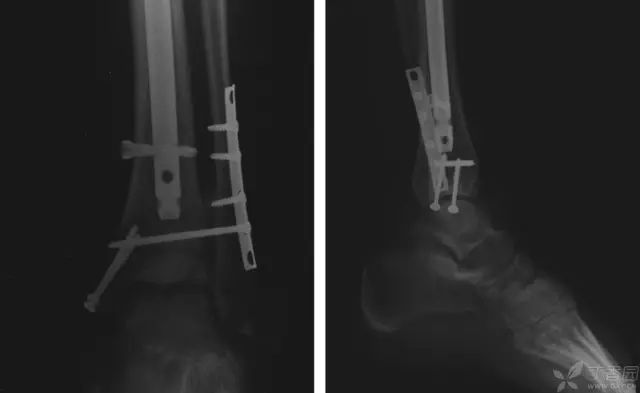

病例二[9]

33 岁男性,车祸多发伤。左踝严重污染,几乎环形创口,胫骨远端 20 cm 缺损

游离骨块生理盐水灌洗,保持湿润,4 小时内紧急手术。术中对创口和游离骨块各用 12L 生理盐水灌洗,彻底清创。外固定支架固定,创口松散地缝合

原计划 48 小时再次灌洗,因身体情况不稳定,10 天后再次进手术室清创灌洗,方法如前;48 小时后进行了第三次灌洗,然后进行了内固定,闭合创口。

3 个月后创口无感染迹象,骨折处无压痛

6 个月后,骨折线模糊,独立行走

18 个月恢复工作